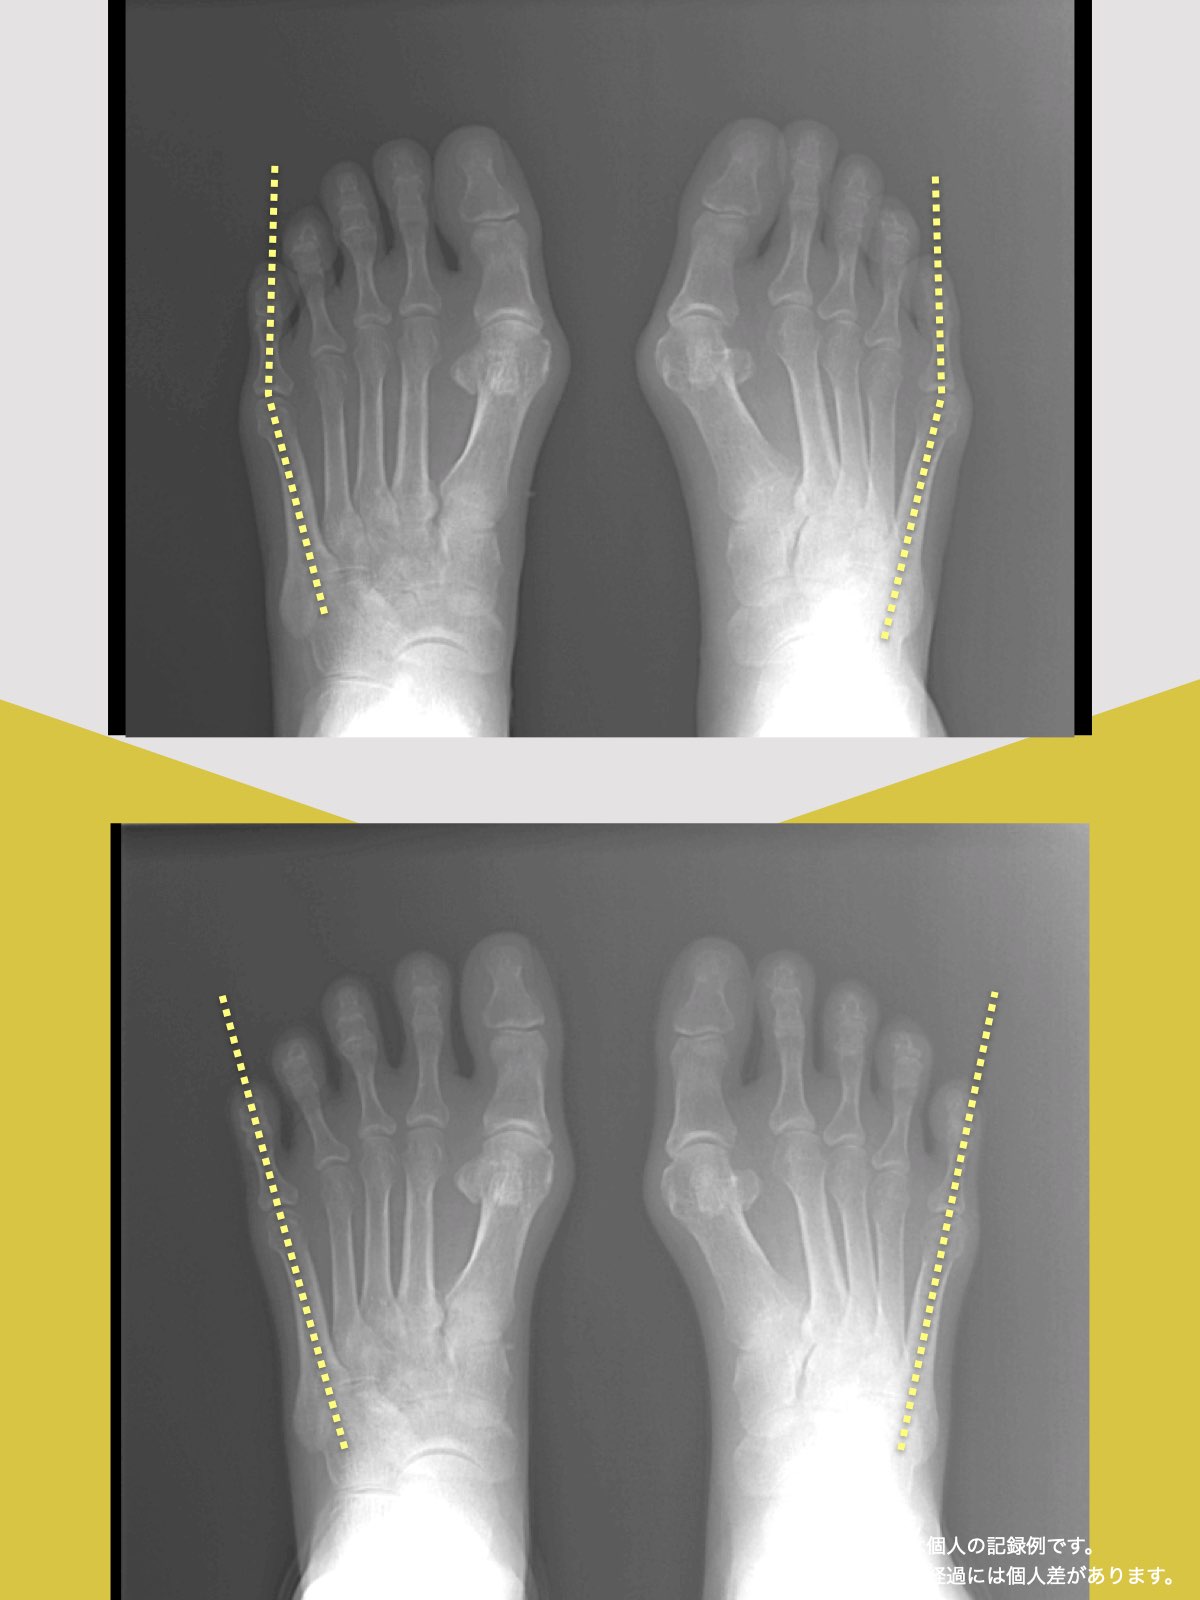

東京大学名誉教授・石井直方先生(運動生理学)とともに、2020〜2022年に行った共同研究では、YOSHIRO SOCKSの着用および、ひろのば体操を日常的に実践された方を対象に、内反小趾などに関する足指の状態や角度の変化について評価を行いました。

内反小趾角

開始時の内反小趾角は25.1°

8週間後の内反小趾角は5.3°

8週間目の平均値では、開始時と比べて、内反小趾角に19.8°の変化がみられました。

※開始前と8週間目の平均値の差

※グラフは臨床試験における平均値の推移を示したものです

※結果には個人差があり、すべての方に同様の変化が生じるわけではありません

※本データは石井直方名誉教授(東京大学)の助言を得て実施された研究に基づくものです